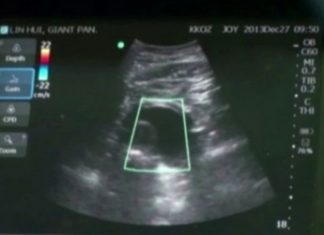

Giant panda to deliver baby, second cub for Thailand

CHIANG MAI, Dec 30 – Lin Hui, a giant panda on loan from China, is due to give birth next month after being artificially...